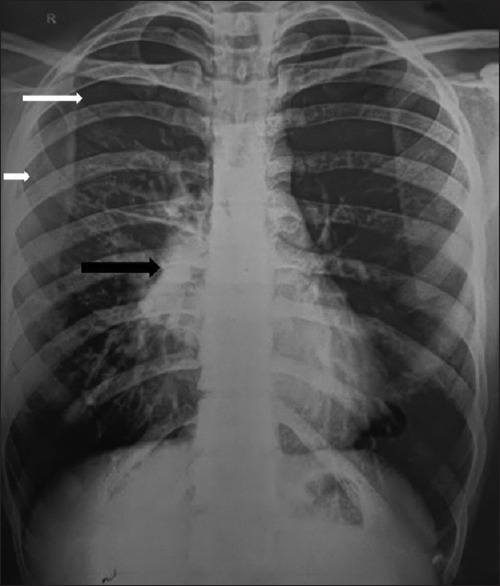

Abstract: In patients with severe asthma with allergic bronchopulmonary aspergillosis (ABPA), a variety of radiological manifestations are seen. Pleural involvement is rare, and a very few case reports of secondary spontaneous pneumothorax have been reported in the literature. Here, we report an even rarer case of secondary spontaneous pneumothorax in a patient of ABPA 'without asthma'.